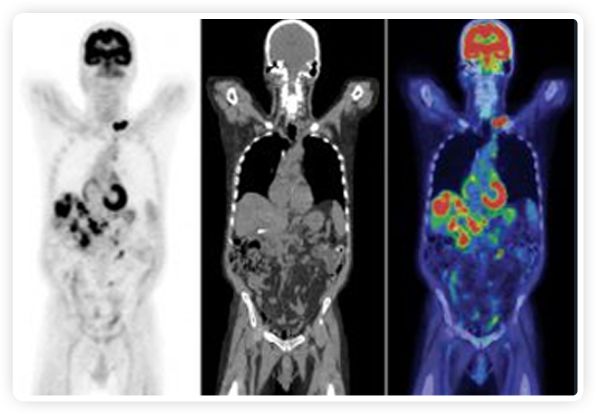

提起放療設備的引導系統(tǒng),大家通常會想到結構性成像的CT或核磁。但你有沒有想過用功能性成像來引導放療呢?美國的一家醫(yī)療器械公司從2011年就致力于研究開發(fā)用PET提供生物學指導放射治療的設備BgRT。BgRT能實時利用癌癥的生物學特征作為信號指導治療全身腫瘤。

PET提供生物學信息

正電子發(fā)射斷層掃描(PET)是癌癥檢測中已建立的成像標準,與其他成像方式相比,PET能提供高靈敏度和特異性的圖像。

到目前為止,放射腫瘤學中(使用的圖像主要是結構性的,而PET圖像可以提供生物學信息。通過使用注射示蹤劑,例如18-FDG,PET可以描繪腫瘤的代謝活性,使其“點亮”。(FDG是用于可視化癌癥代謝的最廣泛使用的示蹤劑。與正常組織相比,腫瘤細胞保留更高水平的FDG。)不同的PET示蹤劑可以識別腫瘤的不同生物學特征,例如特定生物標志物抗原(例如,PSMA)或甚至探測免疫系統(tǒng)本身(例如,PDL1表達或活化的T細胞)。

PET+放療共同治療

RefleXion將PET成像與立體定向放射治療相結合。在注射示蹤劑后,RefleXion的技術基于示蹤劑信號實時地在一個或多個目標上引導治療性X射線。使用這種專有方法,RefleXion的平臺有可能比現(xiàn)有系統(tǒng)向癌癥病變提供更高劑量的輻射,并改善周圍健康組織的保護。